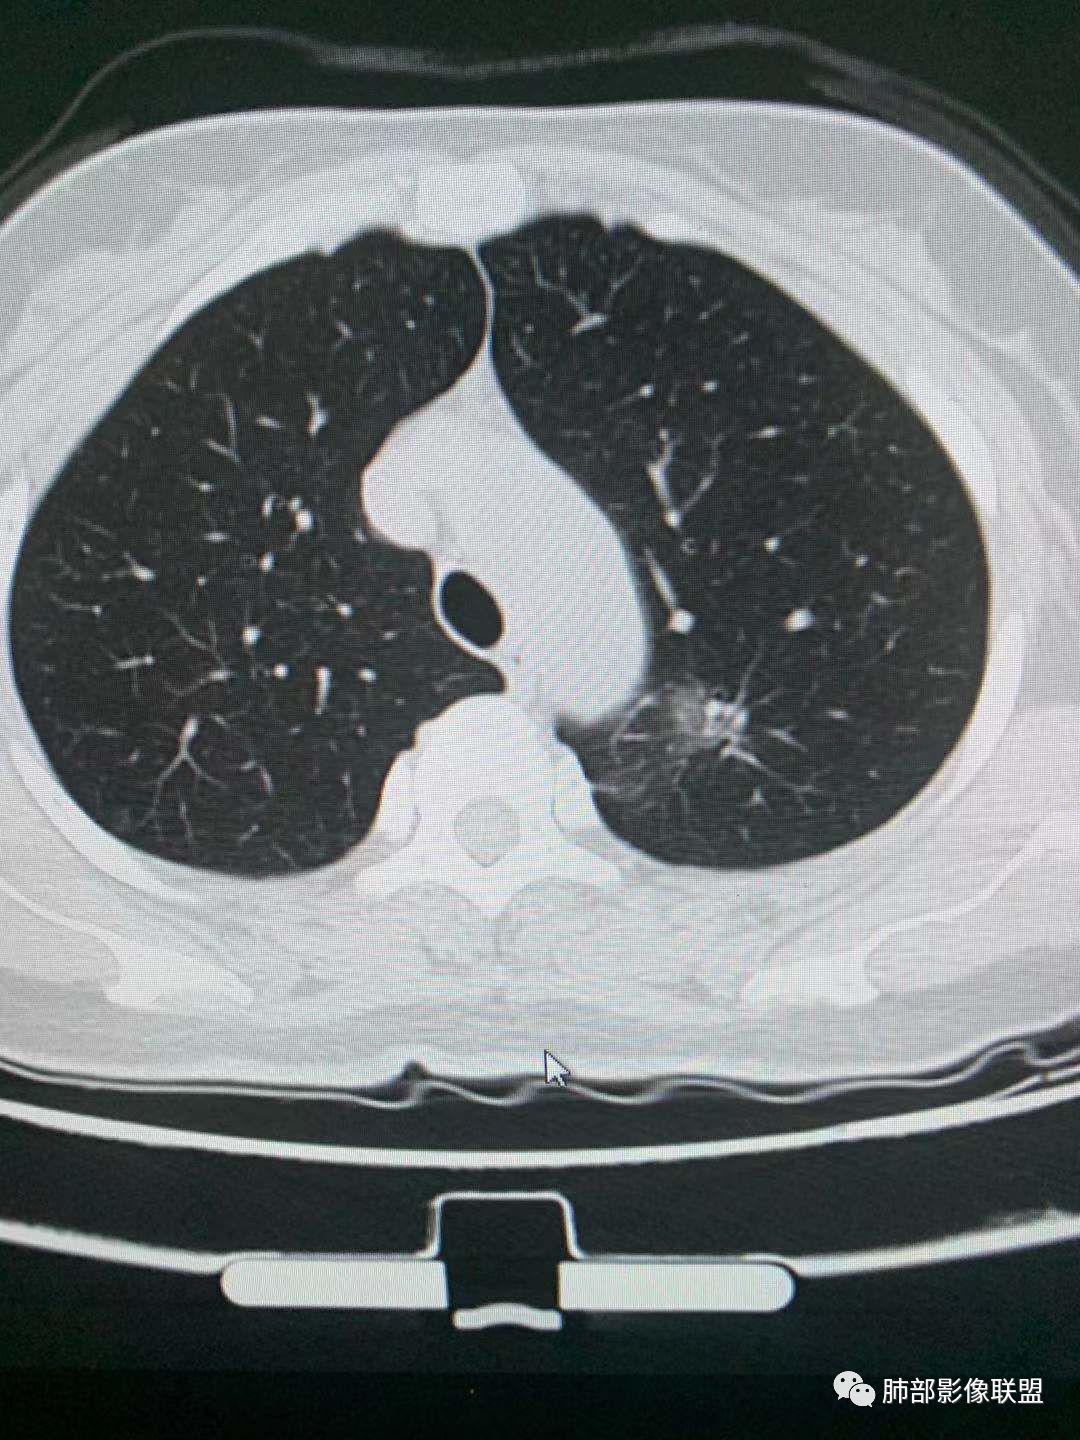

二、看第二个结节

1、密度?

2、边界?

3、收缩力?

4、血管?

5、大小、内部结构、CT值

金豆

纯磨玻璃 边界清

小兜

三个石头

纯磨玻璃,能画出轮廓,但是感觉边缘又比较模糊,是层厚原因吗,收缩力弱,血管进入

心灵鸡汤

三、看看这一个

1、密度:PGGN?MGGN?

这个密度要高一些,混合磨玻璃结节

MGGN,比上面两个密度高

这个结节中间密度稍高一些 不像纯的

都认为mggn,都觉得密度高了?

三.右肺上叶胸膜下结节及左肺上叶血管旁结节,尽管都是磨玻璃密度,但都比较小且边缘特征不明显,恶性征象未显露,处置并无特殊,定期复查!